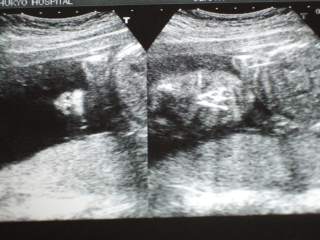

6ヶ月健診に行って来ました♪何だか今日は先生がお忙しかったようで、楽しみにしていた超音波検査もあっという間に終わってしまったような・・・(いや、前回が異様に長かっただけ・・・?)お腹の張りについても、自分では良く解らないので張っているのかどうかを聞いてみたのですが、返って来たのはこんな回答・・・「う~ん、まぁ、お仕事しているからねぇ・・・生理痛みたいな痛みがあったら また来てください。」って、回答になってないよぉ~(まぁ、要するに心配するほどの事はないっていうことだね・・・と、勝手に理解)気を取り直して、今日の赤ちゃん写真です♪(注:心霊写真ではありません~)良く解らないですよねぇ・・・顔を右に傾けて見てください~左側にあるのが、鼻(の穴)の写真です♪ちゃんと鼻の穴が2つあってヨカッタァ・・・って喜んでいる場合じゃなくって何でそこで止めたのだ!先生~もっと違う写真が良かったなぁ・・・なんていうのは贅沢?右側の写真は、顔全体の写真です♪目も鼻も口も、うっすらですけど写ってますこれを見て相棒は・・・「あ!この写真は俺そっくりだぁ~♪」って、親バカですよね♪相棒はめっちゃ鼻筋が通っているので出来れば似て欲しいけど・・・まだ解らないぞぉ~私に似て丸い鼻かもしれないぞぉ~取り合えず、アップでも撮ってみましたけど、今のカメラではこれが限界ですそれと、もう一枚は・・・うーん・・・良く解りませんね(汗)赤ちゃんが大きくなってくると、写真でも何を撮っているか解らなくなるようですが(先生は解っているのでしょうけど・・・)この写真も、左側に頭があって、上の方に背骨があって・・・くらいしか解りませんねまぁ、取り合えず、私も赤ちゃんも順調っていうことで、無事健診が終わって良かったです♪(体重増加が恐ろしい事になっているのですけど、この際考えないことにしましょう・・・)